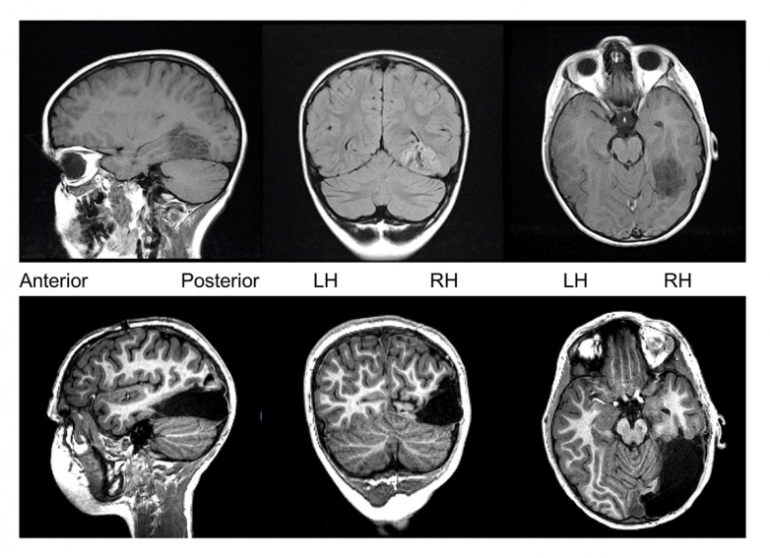

當男孩 6 歲時,外科醫生大約移除男孩大腦右半邊的三分之一。移除的部分是管理感官輸入的區域,包括視覺和聽覺。醫生希望手術可以停止男孩的癲癇發作,但同時也擔心這可能會阻礙男孩的發育。令人意外地,這似乎並沒有發生。

現在距離手術日已經三年了,男孩的表現比醫生所預期的要好很多。他的認知和智力與同年齡層的孩子相當,這一切都要歸功於他的左腦扮演雙重功能的重要角色。通過監測他的大腦活動,醫生們看到男孩大腦的左側已經重新排列,以幫助處理重要的資訊,例如臉部識別。